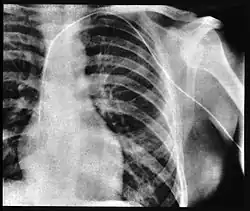

Er nutzte den Zugang über die linke Vena cephalica, eine große Blutader an der Außenseite des Oberarms. Er schob den Katheter 65 Zentimeter weit bis in die rechte Herzkammer und führte ihn durch die Oberarmvene in die Vena subclavia und von dort durch die Vena brachiocephalica und die obere Hohlvene (Vena cava superior) in den rechten Herzvorhof.[22] Dies dokumentierte er mit einer Röntgenaufnahme,[22] für die er (nach der Schilderung in der Autobiografie) mit dem eingeführten Katheter in den Röntgenkeller der Klinik ging und mit Hilfe einer Röntgenschwester ein Bild von dem Schlauch in der rechten Herzkammer machte.[4][12][21]